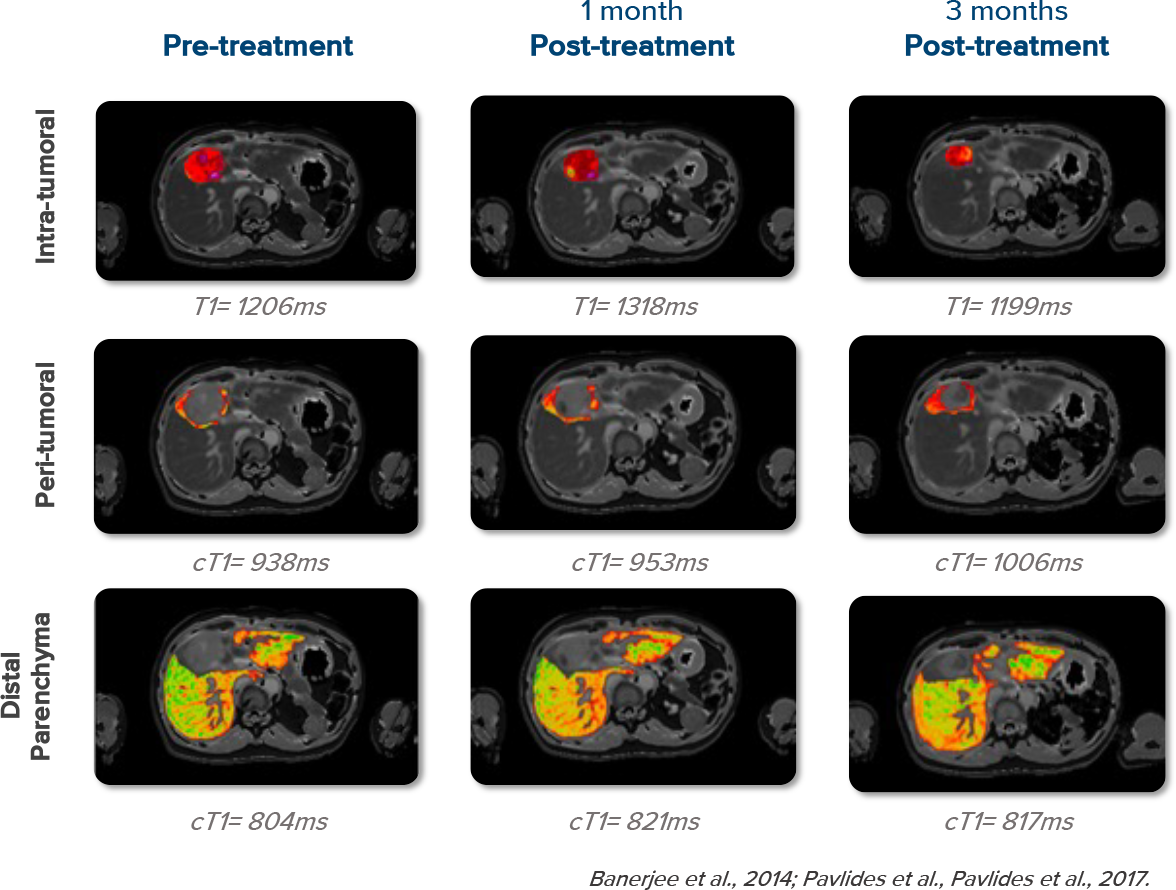

Monitoring with cT1

cT1 accurately detects early efficacy signals and pseudo-progression, and quantitatively monitors drug-induced liver injury.